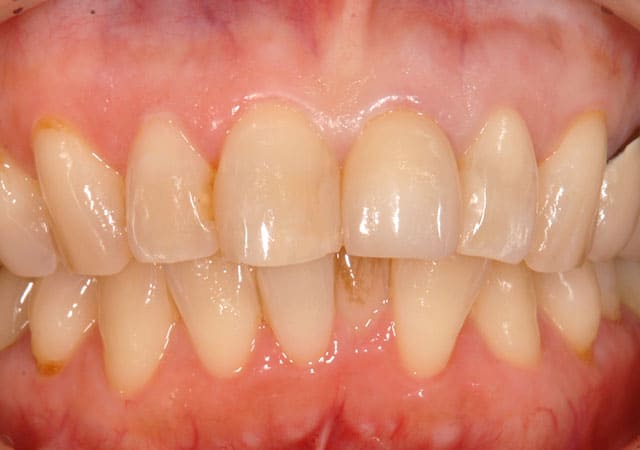

患者さんの希望を反映した補綴物が完成しました。

イボクリーンでアルコールでは除去できないタンパク質を分解する液体でかぶせものの内面を清潔にします。

患者さんの希望の色味、形となりとても満足いただけました。